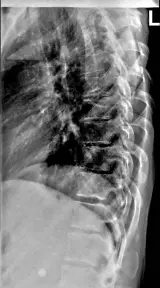

Over 2,100 interactive radiology cases, curated by radiologists for your level of training. Scroll, window, and view cases full screen — just like on PACS. Click linked findings in each writeup to jump straight to them on the image. Cases include sample reports, a focused discussion section, original illustrations, and videos.

Casos totalmente interativos com as ferramentas que você espera em um PACS — rolagem, ajuste de janela, zoom, movimentação, medidas, ROIs e modo de tela cheia.

Anotações detalhadas destacam os achados principais diretamente nos casos. Clique nos achados vinculados nas descrições dos casos para ir ao local exato no exame.

Role, movimente, ajuste janela e amplie como em uma estação PACS do trabalho